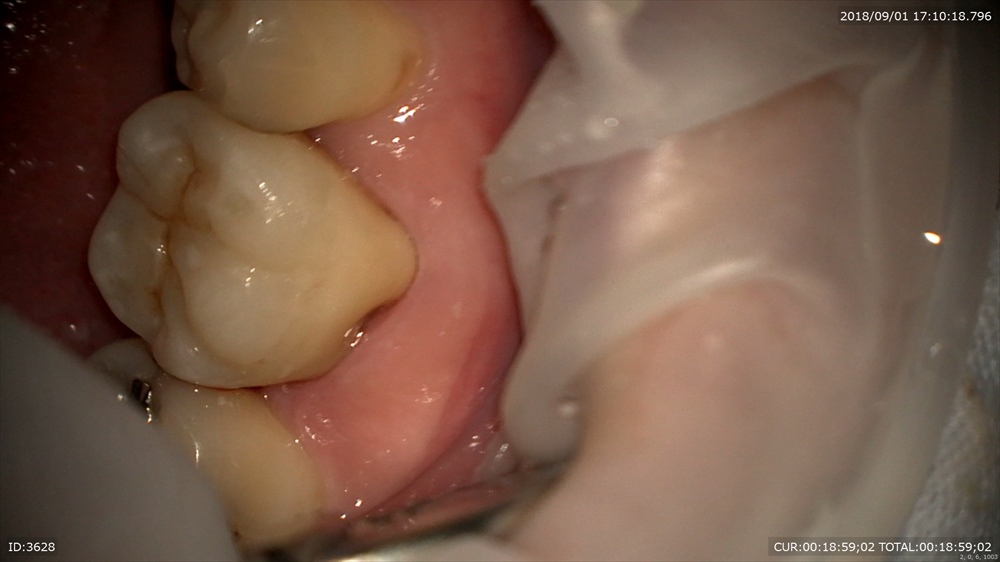

歯周病治療後型取りをして

本日セット 技工士間中先生

少しの段差もありません、

このように重症の虫歯でも抜歯せずに治療ができます。ただし、